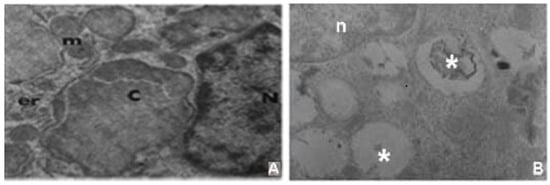

4.2. Putative Glycolipid Storage